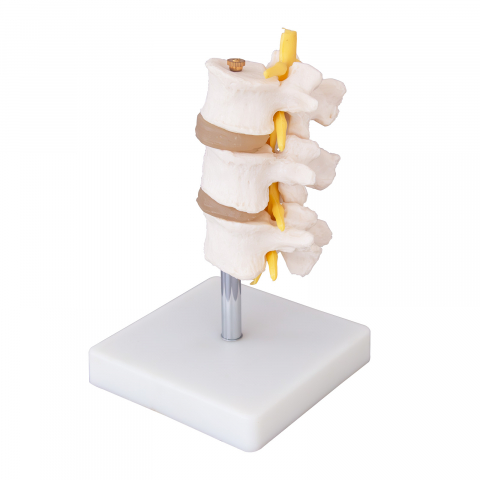

Modelul este conceput din material plastic PVC și este frumos colorat.

Acest model este conceput ca ajutor vizual pentru predarea cursurilor de anatomie umană și igienă. Este folosit pentru a demonstra structura dintelui, la studiul sistemului digestiv în gimnaziu, liceu și școli postliceale medicale.

Acest model are înălțimea de 23-26 cm, prezintă 3 rădăcini, o secțiune longitudinală prin care se poate observa structura interioara a dintelui, este conceput din material plastic PVC și este frumos colorat.